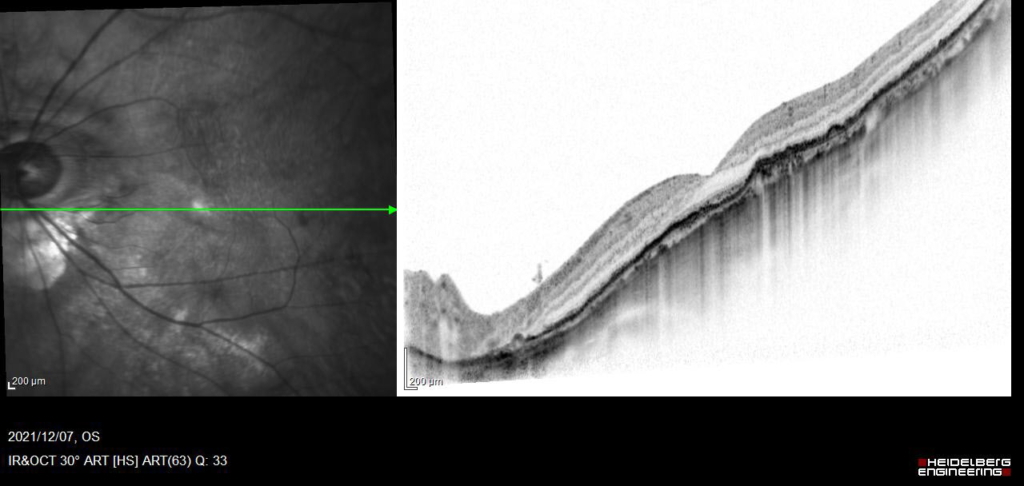

線維血管性 PED fibrovascular PEDは、表面は不整なドーム状隆起を呈する。内部は不均一な中等度から低反射を示し、漿液や出血成分、線維性の層状の中等度反射が混在している。これはRPE下のCNVの存在を示す。

4wで硝子体注射(アフリベルセプト)T&E